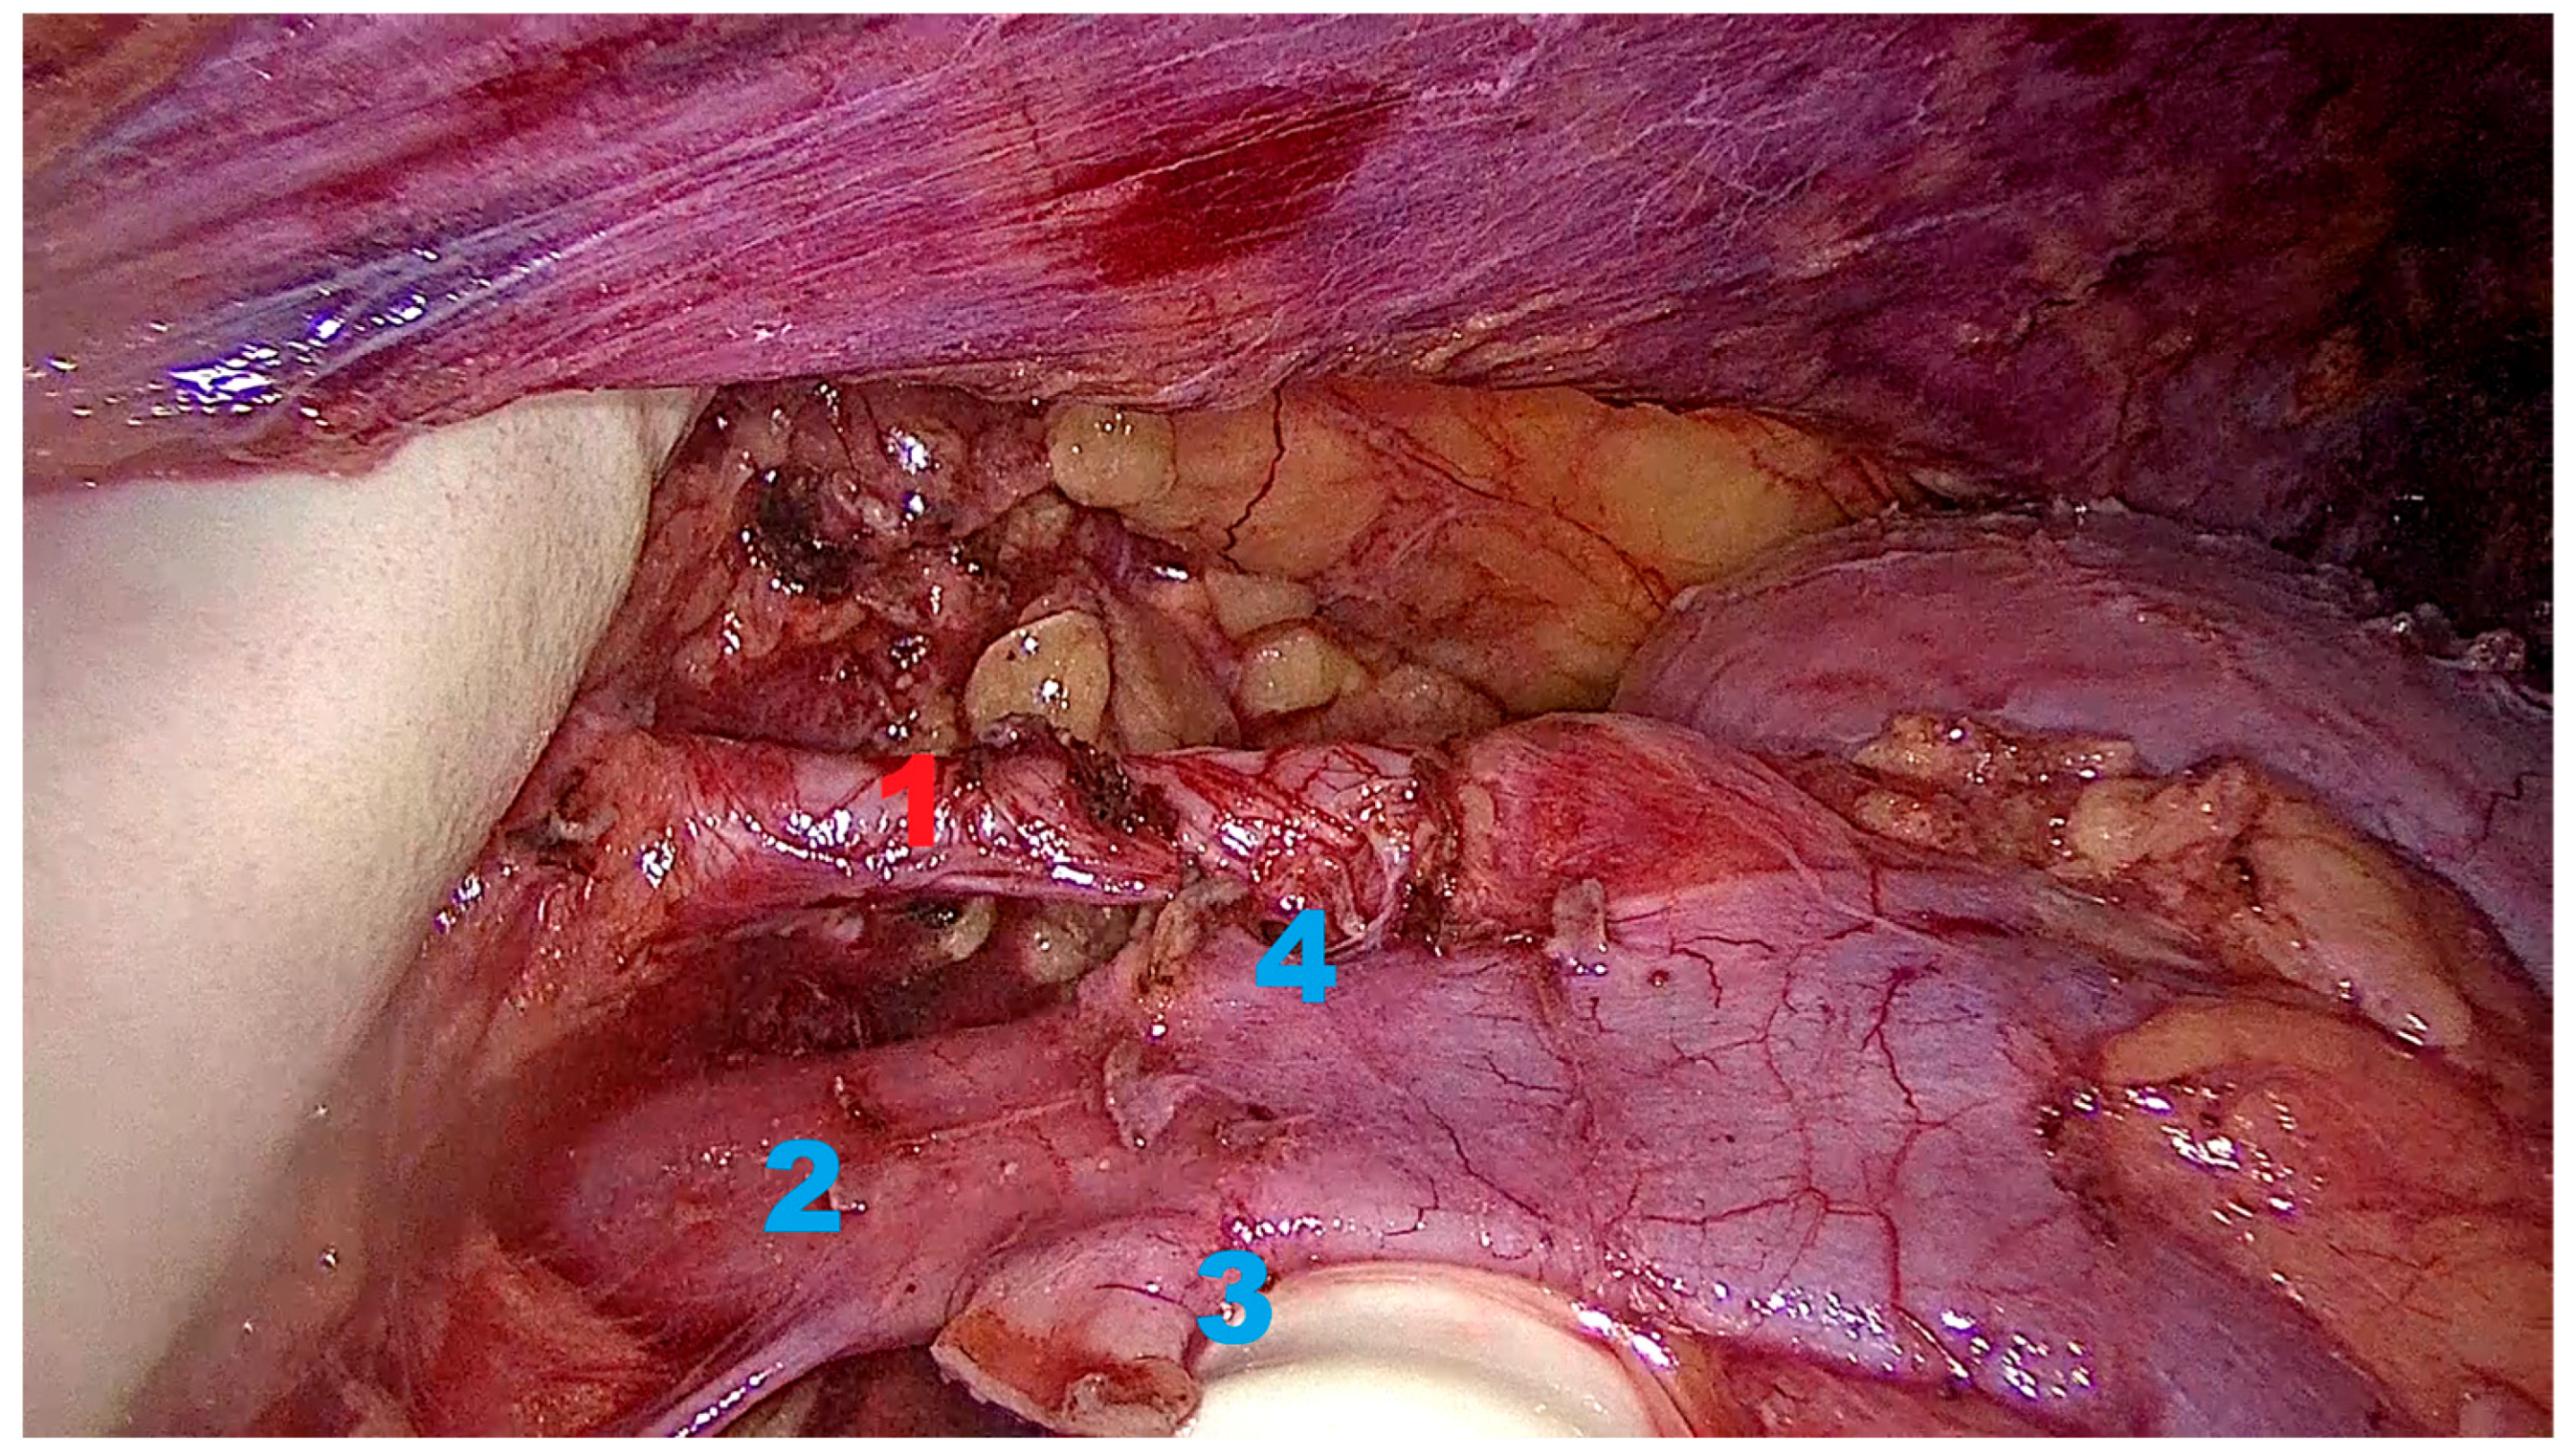

2.6.3. Kidney Mobilization and Hilar Dissection

2.6.4. Graft Procurement and Extraction